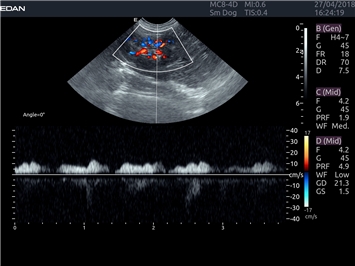

Цветовой допплер:

Да

Постоянно-волновой допплер:

Импульсно-волновой допплер:

Трехмерная реконструкция ЦДК: